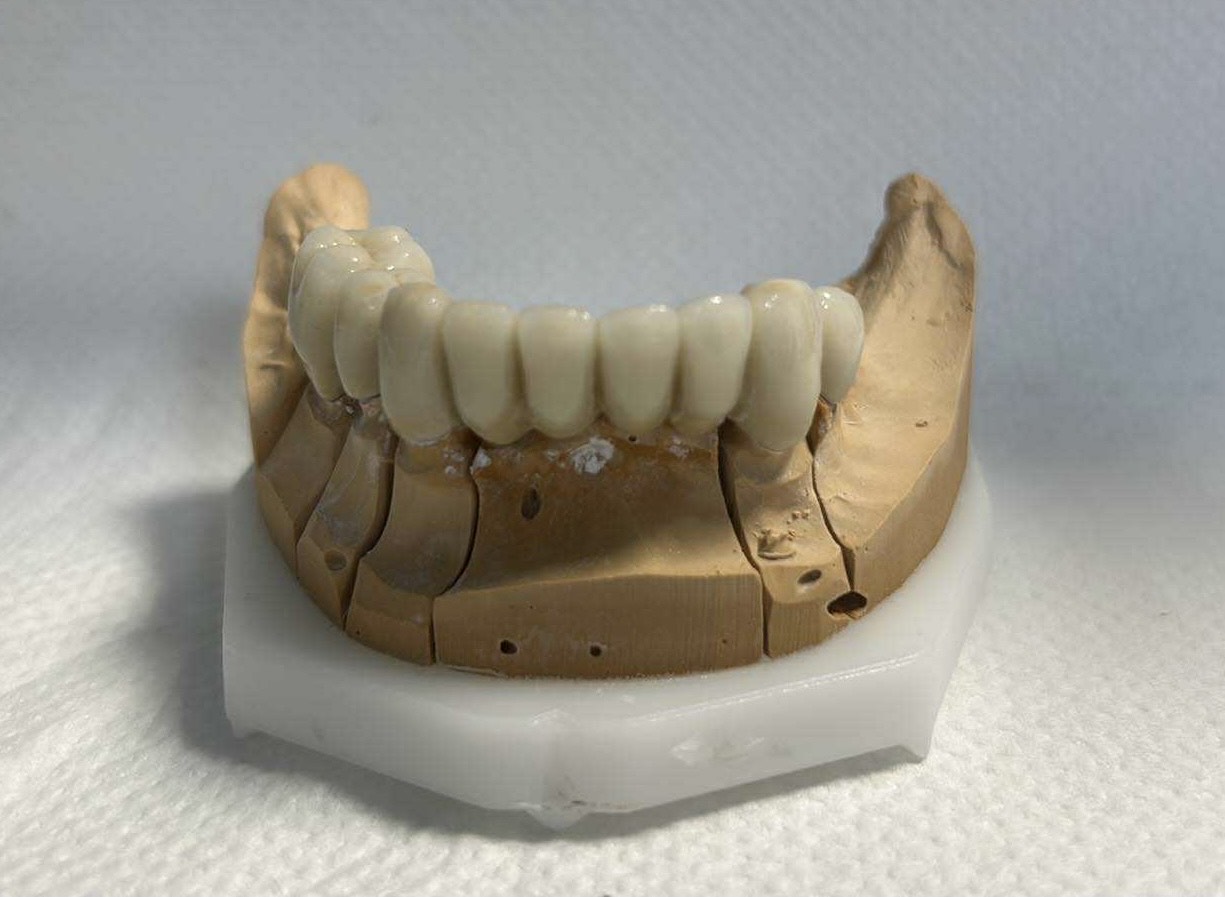

Előtte-utána: Régi alsó fémkerámia körhíd cseréje